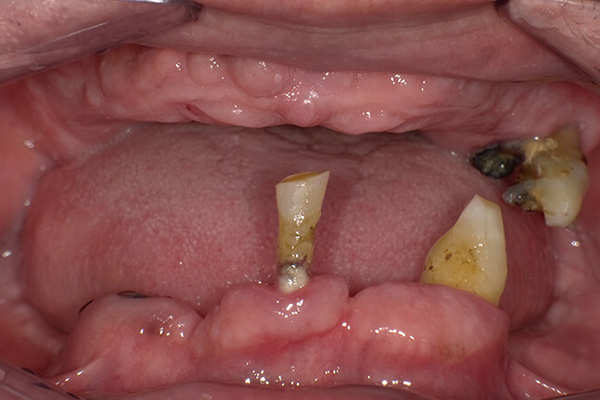

患者様のお悩み 歯がほとんどない状態で、柔らかいものしか食べられない 治療概要 インプラント・オールオン4 歯がほとんどない状態でしたが、患者様は入れ歯も使用しておらず、柔らかいものしか食べられない不便な生 […]